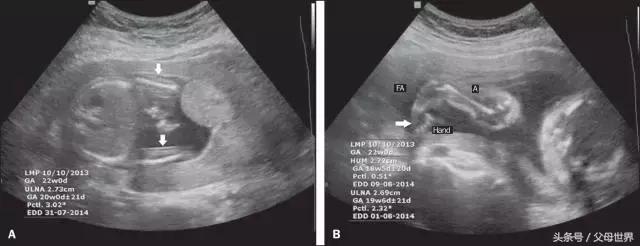

健康的准妈妈在孕期至少要进行两次B超检查,一次在孕20~24周,这是一次非常重要的检查,观察胎儿发育是否存在比较明显的畸形?生长是否符合预产期?胎盘羊水是否正常?另一次在孕32~34周,进一步排查畸形,并观察胎儿在子宫内生长是否正常,以及胎盘羊水等情况变化。

- 监测胎儿生长发育。主要通过测定双顶径(B P D)、头围(H C)、腹围(AC)及股骨长(FL),来判断孕周及胎儿的生长发育情况。此外,落后于正常生长发育的胎儿,有时还需测量身体各部分的比例,如头围与腹围的比例,能够更好地了解胎儿的生长情况。

- 发现胎儿畸形。B超检查是发现胎儿畸形的一个重要的手段,随着孕周的增加和胎儿的生长发育,胎儿某些器官的发育异常能够逐渐显现出来,如较大的心脏结构异常(如一部分先天性心脏病)、消化道畸形、神经管畸形、脊柱裂等。如果在此期间发现胎儿畸形,容易终止妊娠,所以定期进行B超检查十分重要。